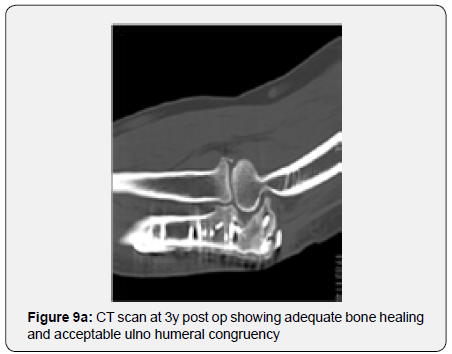

The remaining part of the bone graft was used in the non articular radial sided metaphyseal defect. The wound was then thoroughly irrigated and closed. The Patient was held in a cast for 2 weeks for soft tissue protection and from the 2nd to the 3rd Week he started passive range of motion exercises. After the 3rd Post operative week, the patient enrolled a physical therapy rehabilitation program, not directly controlled by the surgeon. At 3 Months post op the patient had regained adequate range of motion (flexion 120, extension15º, prono supination 90-0- 90º) and the x ray showed a stable elbow with graft integration and greater sigmoid notch articular congruence despite some heterotopic bone ossification/calcification in the olecranon fossa that might preclude full extension (Figures 7a & 7b). The Patient returned to his work 5 Months after surgery. At 3 Years post op he has no pain and has a ROM (Flexion 140º, extension-15º, prono supination 90-0-90) that allows him to do all of his daily living activities (Figures 8a & 8b). His CT Scan shows the healed bone graft and adequate ulno-humeral congruency (Figures 9a & 9b), Despite some degenerative changes are evident. He achieved a Mayo Elbow Performance Score (7) of 100.